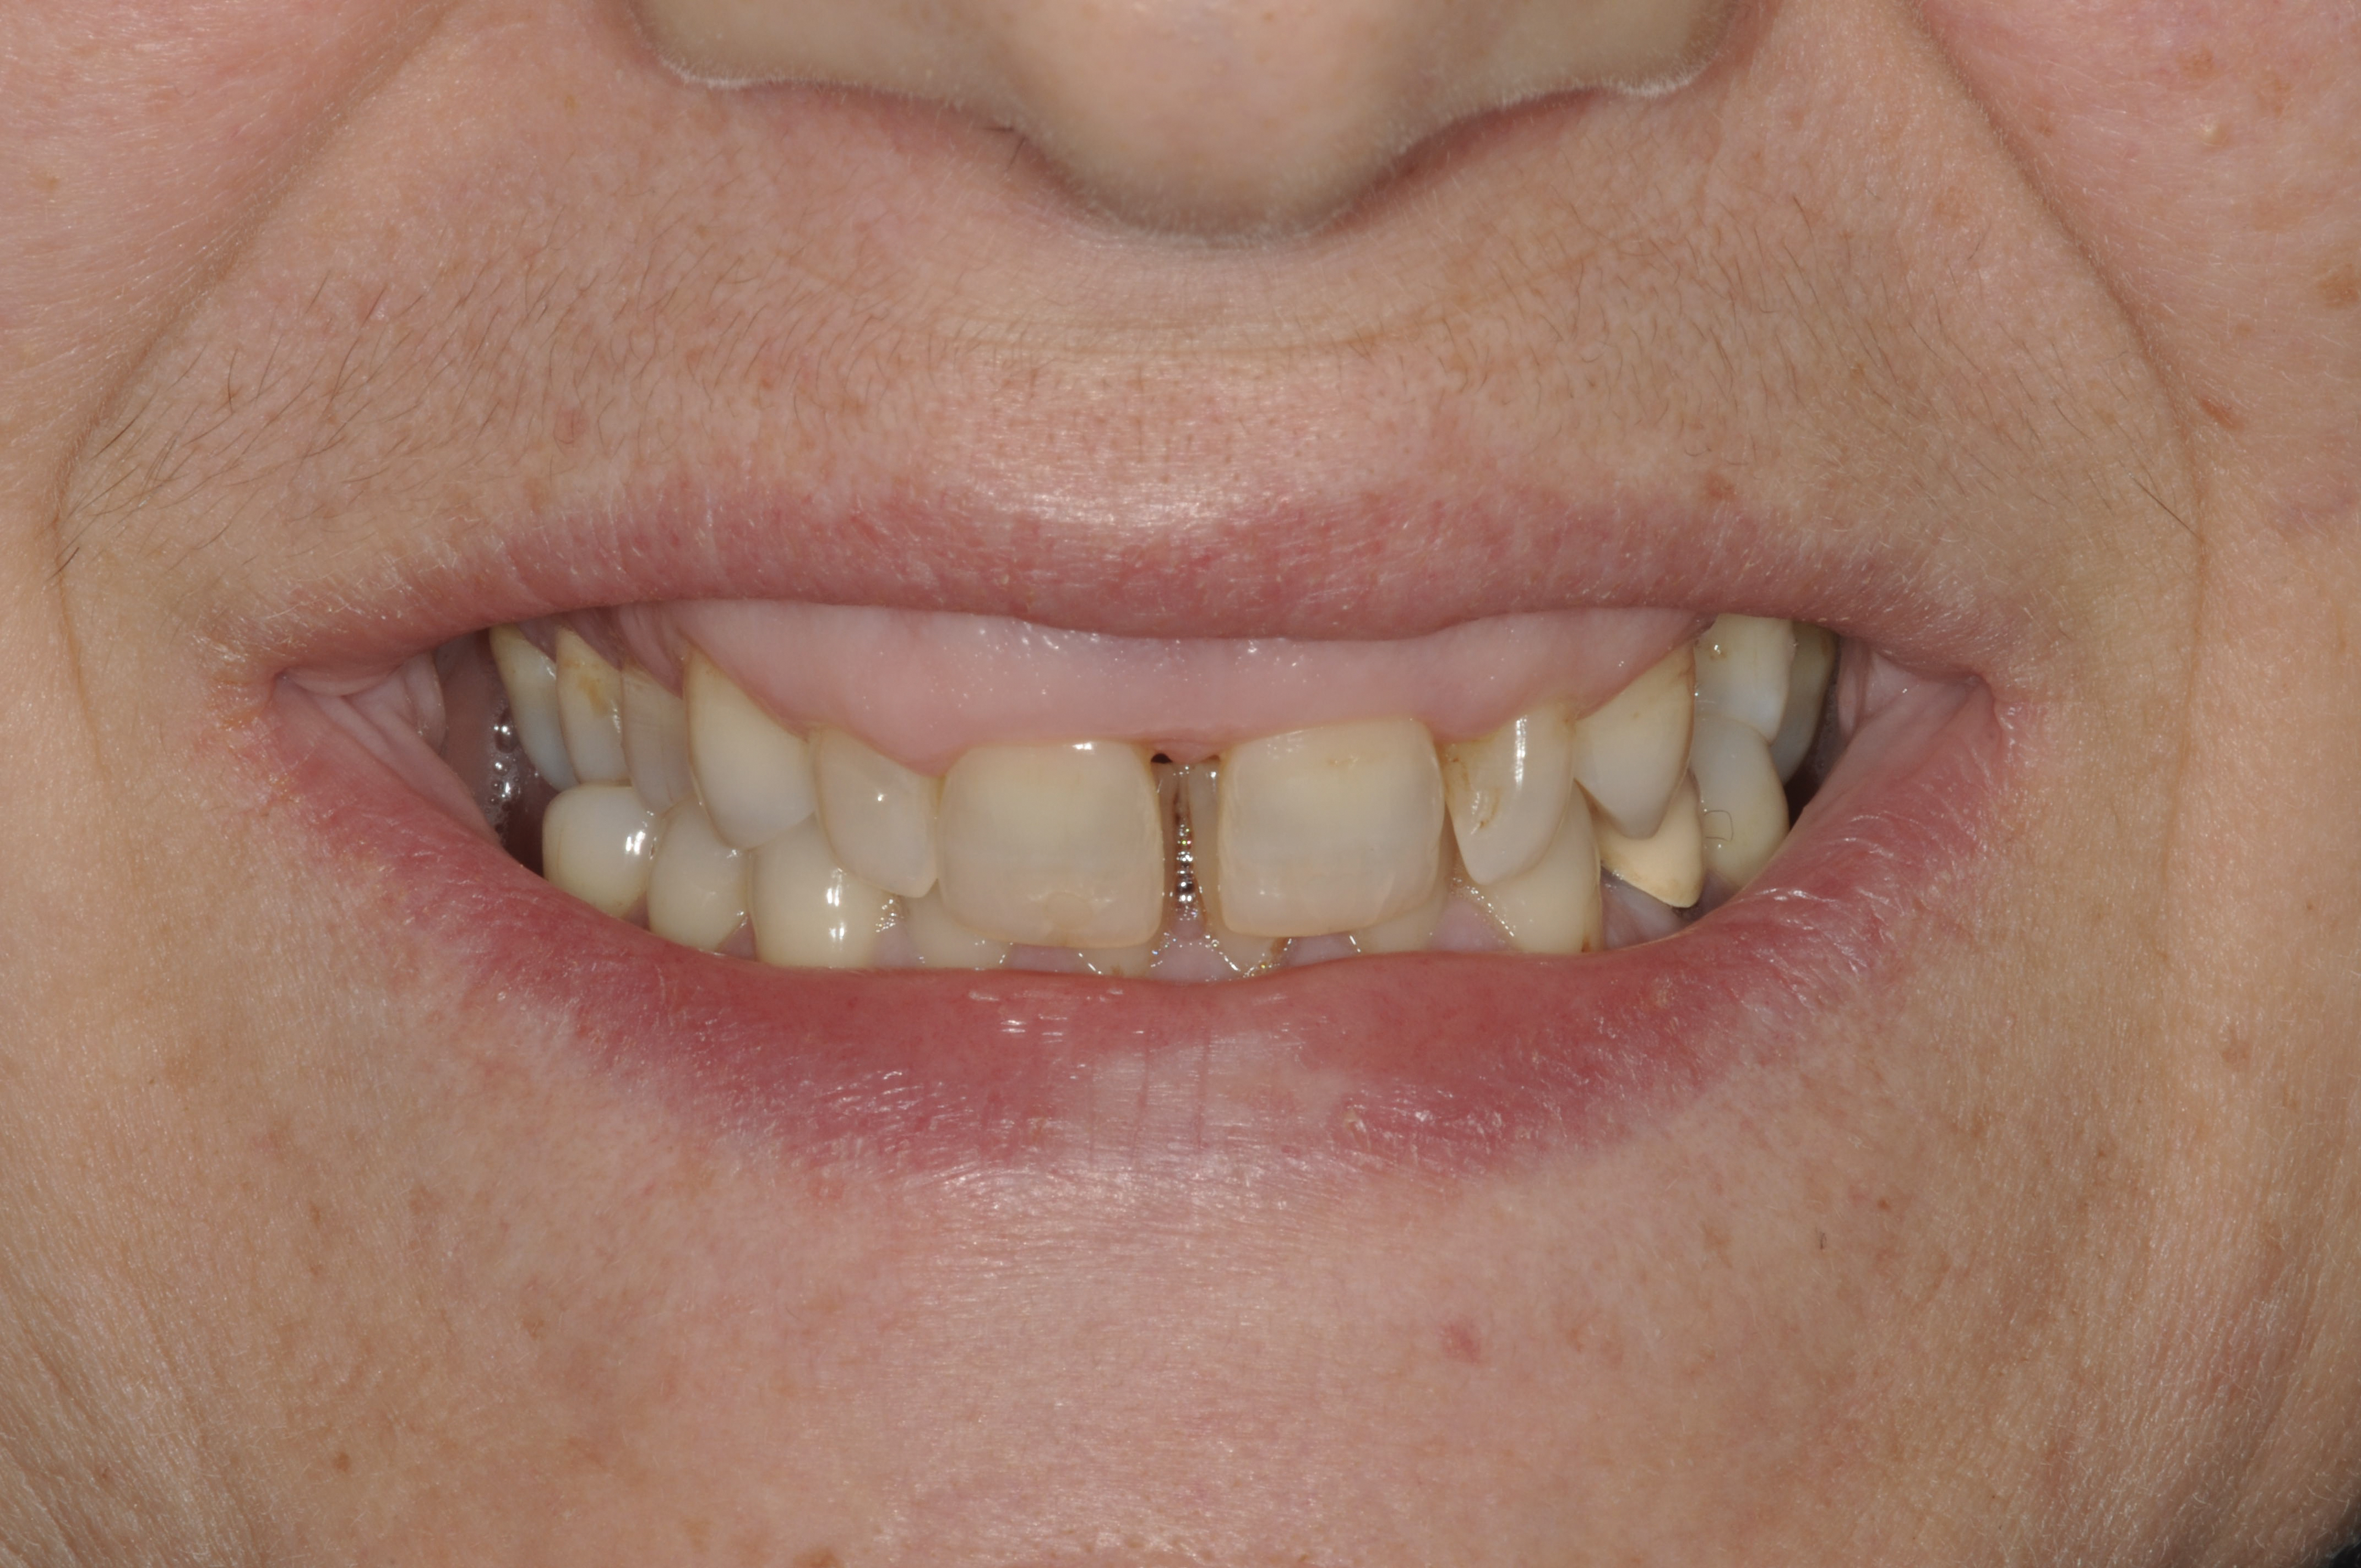

The authors consider GS and STS as two esthetic smile alterations that often coexist and have similar or coincident etio-anatomo–pathological origin and need to be diagnosed simultaneously with identical guidelines. Some of the causes of GS—including deep bite and overeruption and compensatory eruption (wear/erosion) in teeth, as well as gingival hyperplasia and altered active/passive eruption in gingiva—can also be identified in STS; however, vice versa is not the case. The aim of this article is to propose a classification of such adult patients and briefly describe a diagnostic process to use with this classification, and to identify a correct treatment plan that can lead to a successful treatment outcome (Figure 2).

Fig 2. Resolution of gummy smile after treatment in patient shown in Fig 1.

Figure 2